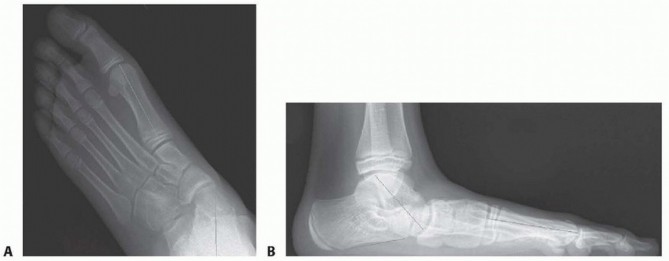

POSTOPERATIVE CARE The incisions are closed with absorbable sutures.A well-padded, short-leg, non-weight-bearing cast is applied and bivalved to allow for swelling overnight. Radiographs in the cast are obtained ( FIG 5).The patient is discharged from the hospital the following day after the bivalved cast is overwrapped with cast material.The patient is immobilized in a below-knee cast and is not permitted to bear weight on the operated extremity for 8 weeks.At 6 weeks, the cast is removed to obtain simulated standing AP and lateral radiographs and to remove the Steinmann pin. Another below-the-knee, non-weight-bearing cast is applied.Upon removal of this cast 2 weeks later, final simulated standing AP and lateral radiographs are obtained. Over-the-counter arch supports are used indefinitely.Physical therapy is rarely needed. ## OUTCOMES The calcaneal lengthening osteotomy has the best reported long-term results of any procedure that has been used to correct flatfoot deformity.It has been shown to correct all components of even severe valgus-eversion deformity of the hindfoot, restore function of the subtalar complex, relieve symptoms, and, at least

theoretically, protect the ankle and midtarsal joints from early degenerative arthrosis by avoiding arthrodesis. ### FIG 5 • Final radiographs in the bivalved cast. A. On the AP view, note the correction of the external rotation deformity at the talonavicular joint as also assessed by the talo-first metatarsal angle. B. The lateral view demonstrates dorsiflexion of the talus, alignment at the talonavicular joint, correction of the talo-first metatarsal angle, and normalization of the calcaneal pitch. (From Mosca VS. Calcaneal lengthening osteotomy for valgus deformity of the hindfoot. In: Tolo V, Skaggs D, eds. Master Techniques in Orthopaedic Surgery: Pediatric Orthopaedics. Philadelphia: Lippincott Williams & Wilkins, 2008:263-276.)